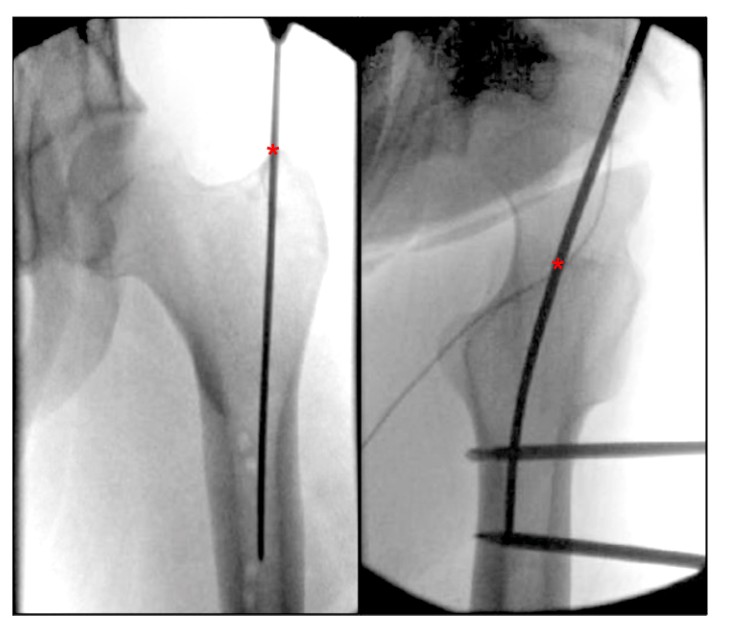

Изучая современную литературу по описанию точек входа бедренного ротора, мы обнаружили отсутствие четко описанных анатомических ориентиров для точки входа ИМН бедренного ротора. Bharti et al. описал точку входа из апикальной вершины большого вертела как медиальную по отношению к костномозговой полости в ортостатическом положении и как центр большого вертела на одной линии с центром костномозговой полости бедренной кости в латеральном положении (рис. 4), а альтернативное описание точки входа в большой вертел на боковой проекции бедра находится в роторе между передней третью и задними двумя третями ротор. Георгиадис и др. описал точку входа иглы как самую заднюю сторону апикально-верхнего края ротора.

РИСУНОК 4. Интраоперационные ортостатические и боковые проекции бедра показывают идеальную точку входа для парамедианного интрамедуллярного штифта большого вертела бедренной кости. «*» указывает на интрамедуллярную точку входа стержня.